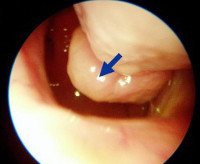

• Эндоскопия полости носа позволяет определить место гипертрофии, состояние слизистого слоя, перегородки и раковины (размер, цвет, форма, васкуляризация). При наличии полипозных образований ткань удаляется для гистологического исследования (биопсии).